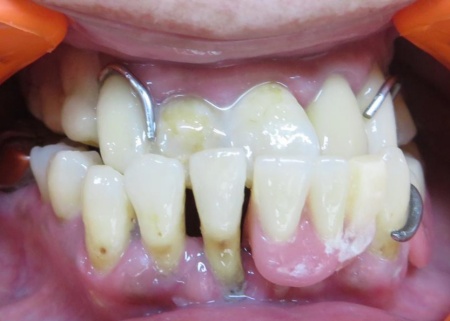

治療前

| カウンセリング・診断結果 | 患者さんの噛み合わせは、下顎が上顎より前に出ている極端な反対咬合の状態でした。 反対咬合は入れ歯を安定させるのが難しく、噛む力が特定の部分に集中しやすいため、入れ歯の破損や変形が起こりやすいとされています。 また、残っている歯の一部には揺れがみられました。 これは、歯を支える骨(歯槽骨)が弱ってきており、歯が噛む力を十分に受け止められなくなっていることが原因です。 お持ちいただいた入れ歯は完全に割れていて、このまま使い続けるのは難しい状態でした。 ただこの段階で新しい入れ歯を作っても、ぐらついている歯が抜けてしまい、短い期間で修理や作り直しが必要になるリスクがあります。 以上のことから、まずは現在の入れ歯を修理して使えるようにしたのち、揺れている歯が自然に抜けて口腔内が落ち着くのを待ったうえで、新しい入れ歯を作製するのが適切だと診断しました。 |

| 行ったご提案・治療内容 | 診断内容をお伝えしたうえで、割れた入れ歯の修理を提案しました。 患者さんはこれまでにも同様の治療を経験されており、治療方針については十分にご理解とご納得いただいています。 まず、技工用の瞬間接着剤で割れた入れ歯を仮止めします。 これは、次の工程で正確な模型を作るための準備です。 次に、仮止めした入れ歯をお口の中に戻して型取りを行い、石こうを用いて模型を作製しました。 模型上で修理を行うことで、口の中でしっかりと合う入れ歯に仕上げることができます。 続いて、割れた部分に対して垂直に交わる向きに金属製の補強線(ワイヤー)を埋め込みました。 補強線をいれることで入れ歯のプラスチック部分にかかる力を吸収・分散できるため、割れにくい構造になります。 最後に、補強後の入れ歯を丁寧に研磨して仕上げを行い、見た目や装着感、噛み合わせに問題がないことを確認して、治療を終了しました。 |